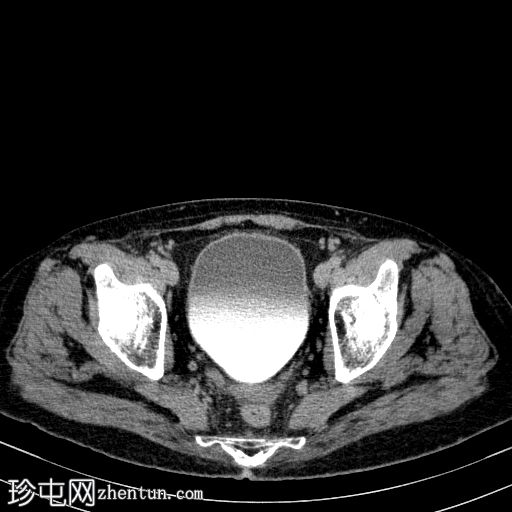

轴向

非造影

胰体尾弥漫性增大,特征为胰腺实质低强化,无明显坏死区域。

该病灶与以下表现相关:

胰周筋膜平面边界不清的污迹,无明显壁形成、气室、固体碎片或血液产物。

病变范围如下:

病变横向延伸至左前肾旁间隙,伴有Gerota筋膜增厚。

病变向下延伸至盆腔。

无肠系膜或脾脏血管阻塞的证据。

未见导管扩张或钙化。